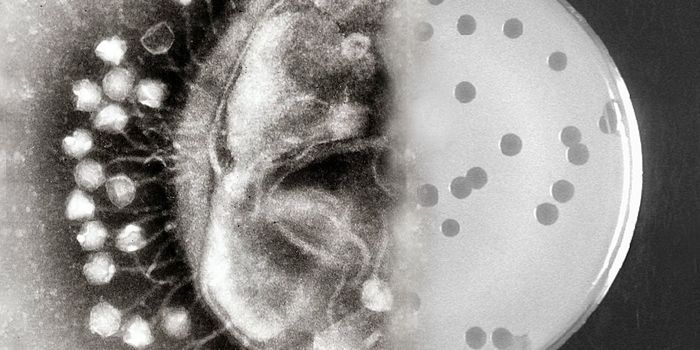

OCT 29, 2016Clinical & Molecular DXDespite frequent cleaning and sterilization, hospitals are notorious hotspots for germs and pathogens. And it’s no ...

MAR 19, 2017MicrobiologyIt can be incredibly challenging to give a patient the proper treatment when they are infected by an antibiotic-resistan ...

OCT 17, 2021MicrobiologyThe world is full of microorganisms. Luckily, most pose no threat to us. But some harmless bacteria have the potential t ...